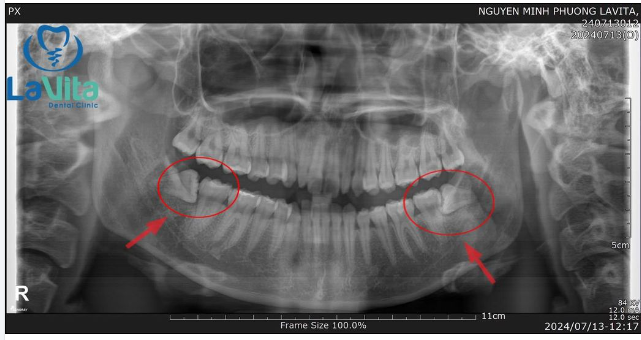

VIÊM LỢI TRÙM DO RĂNG KHÔN VÀ GIẢI XỬ LÝ

Viêm lợi trùm lên răng khôn là một biến chứng rất thường gặp khi răng khôn chưa mọc lên hết, mọc 1 phần (đâm thủng lợi), mọc kẹt trong xương, mọc lệch,… Sau đó xuất hiện túi lợi, che phủ lên bề mặt răng khôn hoặc một phần thân răng khôn, giắt thức ăn, gây nhiễm trùng, sưng tấy, sốt, đau, mưng mủ.

Nhổ răng khôn: Nếu răng khôn mọc kẹt trong xương hoặc mọc lệch, mọc nghiêng,… bác sĩ sẽ chỉ định nhổ răng khôn để ngăn chặn các biến chứng khác có thể xảy ra.